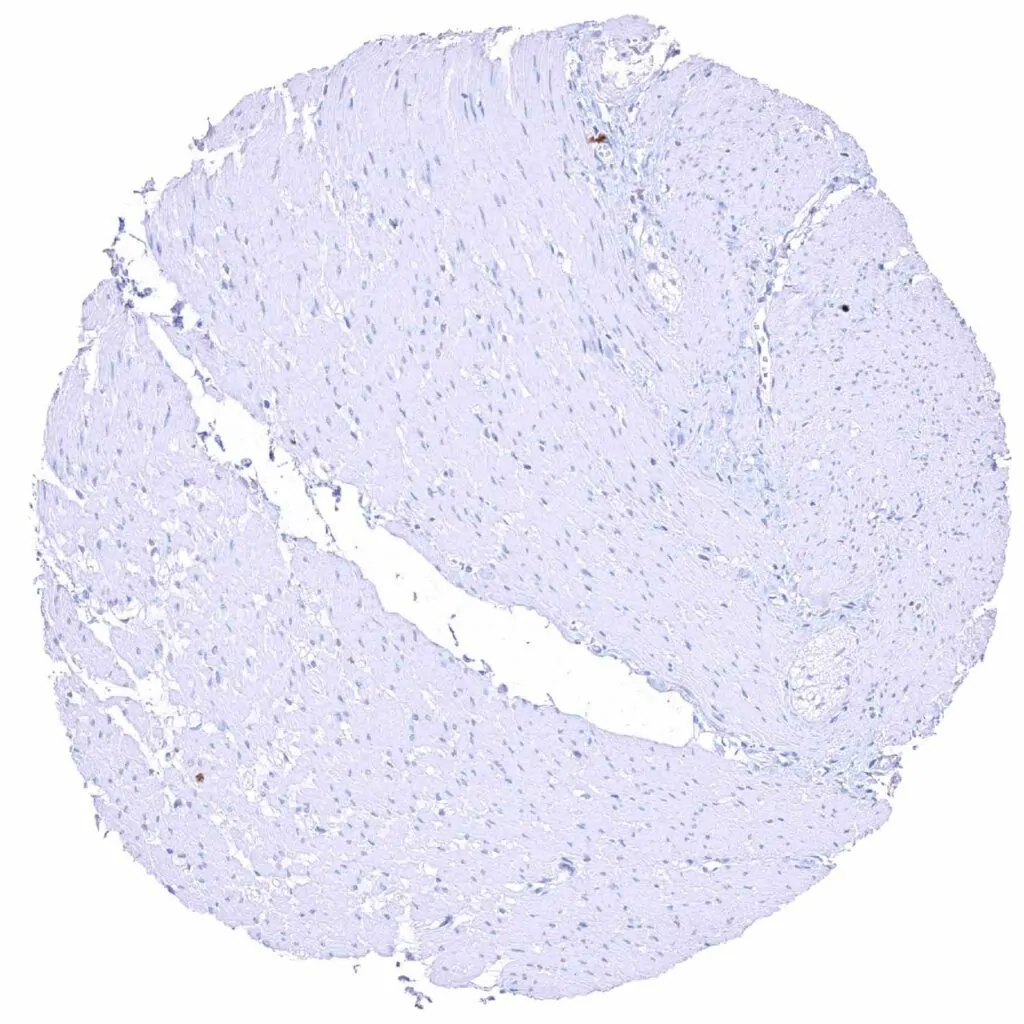

Uterus, myometrium